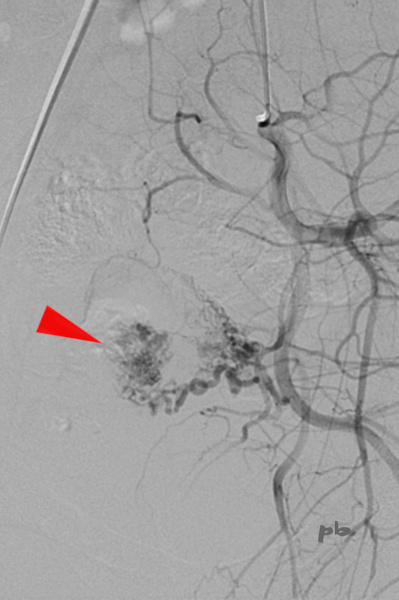

18 – Anomalie vasculaire – Angiographie

(même patiente que 16)

La patiente continuant à saigner de façon importante, et devant le crainte d’être en présence d’une MAV, décision de réaliser une embolisation.

Angiographie : séquence avant embolisation.

Hypervascularisation de la partie gauche de l’utérus (►) aux dépens du segment III de l’artère utérine, correspondant à l’anomalie vasculaire. Pas de MAV.

Embolisation sans difficultés techniques.

Suites simples.